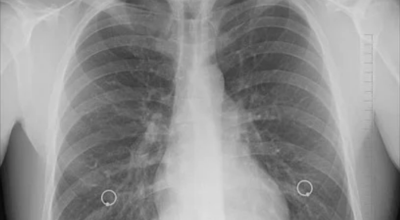

일반인이 근육의 통증과 금이 간 경우의 차이는 거의 판별하기 힘들게 됩니다. 갈비뼈라고 하는 부분이 눈에 보이도록 붓는 것도 아니고, 멍이 들어서 아픈것도 아니기 때문이예요. 가장 정확하게 판별하는 방법은 엑스레이를 찍는 방법이예요.